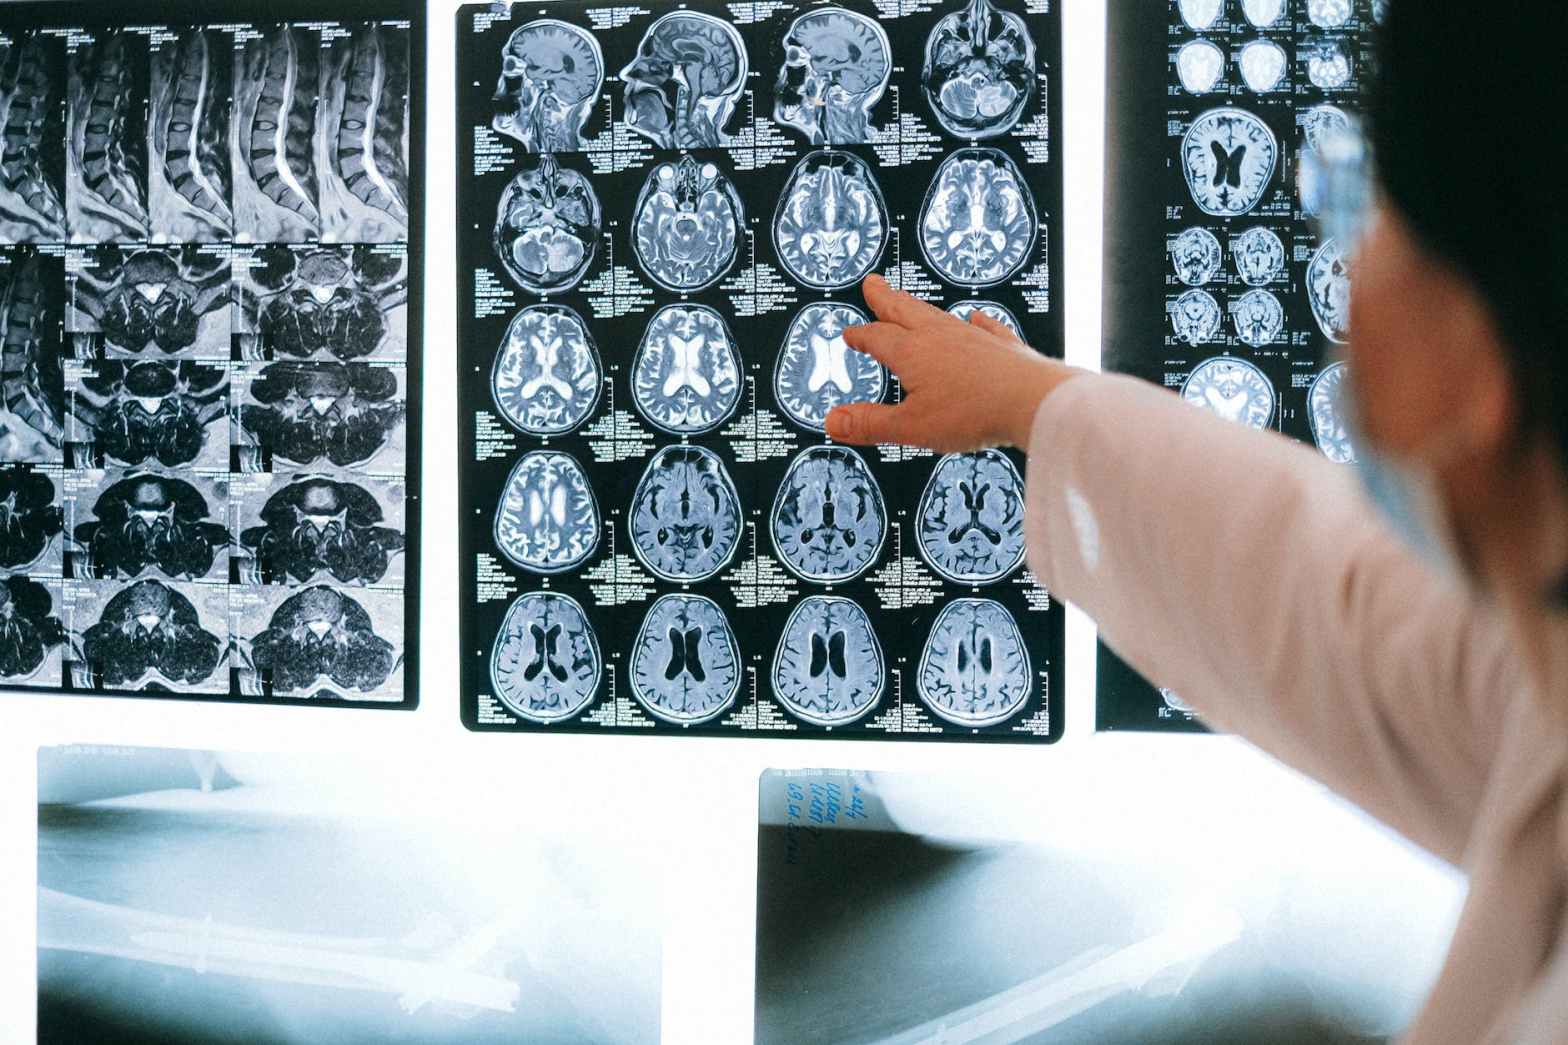

Para investigar esto, se realizó un estudio con 27 mujeres a lo largo de seis ciclos menstruales utilizando resonancia magnética de alta resolución, donde analizaron los efectos de las hormonas ováricas en la memoria y el cerebro. Se descubrió que las fluctuaciones en los niveles de estradiol y progesterona influyen en regiones clave de la memoria, como el hipocampo y la corteza perirrinal. En la primera mitad del ciclo menstrual, los niveles de estradiol se relacionaron positivamente con el volumen de la corteza parahipocampal, región implicada en la memoria espacial y la navegación; mientras que los niveles de progesterona se asociaron positivamente con el volumen del subículo y la corteza perirrinal, regiones involucradas en la consolidación de la memoria y la transferencia de información entre el hipocampo a otras áreas del cerebro y con el procesamiento de la memoria y el reconocimiento de objetos y personas, respectivamente. También se observaron cambios en CA1, una parte del hipocampo, en relación con la interacción entre estradiol y progesterona. En resumen, estas hormonas pueden afectar el tamaño de estas áreas cerebrales en diferentes momentos del ciclo menstrual.

Estos hallazgos tienen implicaciones significativas, ya que sugieren que las hormonas ováricas pueden influir en la plasticidad estructural del cerebro en mujeres en edad reproductiva. Esto puede ser relevante para comprender trastornos neuropsiquiátricos y neurodegenerativos que afectan más a menudo a las mujeres, como la depresión y la demencia. Aunque se necesita más investigación para entender completamente los mecanismos detrás de estos cambios, estudios como este permiten la comprensión del funcionamiento, el bienestar, la salud mental y las particularidades del cerebro femenino, así como para cerrar la brecha de género en las neurociencias haciendo investigación científica equitativa y apreciando la diversidad en la población.